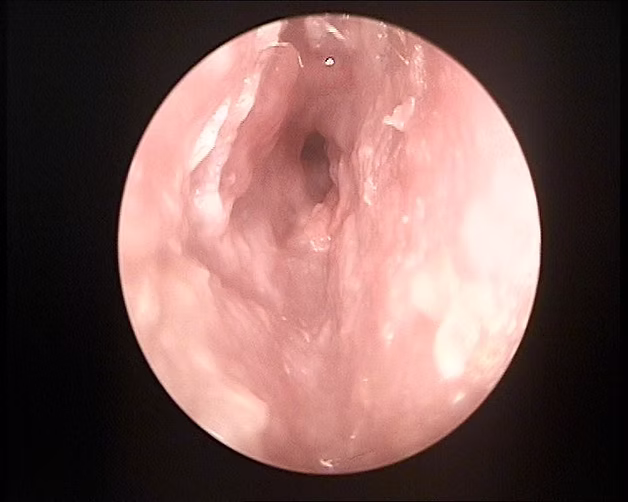

Estenosis del CAE

Se observa piel enferma edematosa y violácea con reducción del diámetro del conducto. Produce supuración, dolor y pérdida de audición.